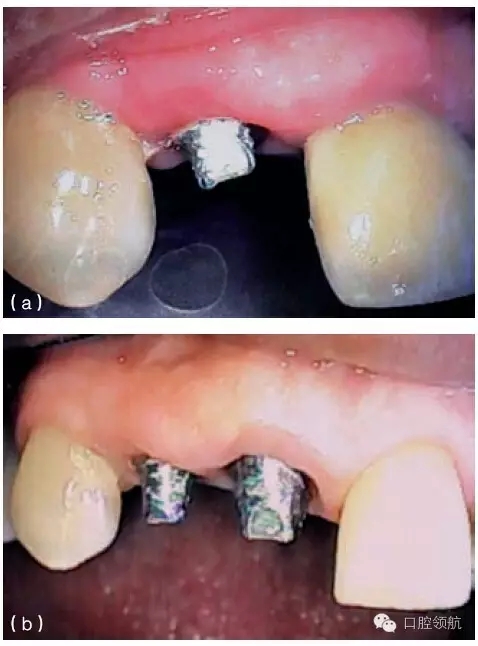

在種植體植入之前,有必要確定最終的修復方案,并且計算放置種植體修復部件所需要的空間。例如,對于單個粘結固位的種植修復體,從種植體平臺到對頜牙,最少需要7mm的空間。這個空間包括以下組成部分:基臺距對頜牙牙合面2mm;對粘結固位來說,即便聚合度非常平行的情況下,也至少需要4.5mm的預備高度,才能滿足固位要求;基臺與種植體交接的拋光肩領需要0.5mm。如果牙合間距離較?。ㄈ?.5~5mm),可以制作螺絲固位修復體(或UCLA的一體化冠)(圖9.23a,b)。實施種植手術時,必須考慮牙齦厚度及牙槽骨的水平。若有需要,可以施行牙槽嵴切除術,以獲得額外的牙合間距離。另外,種植體可以高于、低于或平齊牙槽嵴頂,以便與未來的修復體匹配。但當在修復期間考慮這些問題時,剩下的選擇就非常有限,只能在粘結固位或螺絲固位中選擇一種。有時,可以選磨對頜牙,來獲取少量的修復空間。另外,如果需要恢復垂直高度的話,可以通過升高咬合來獲得牙合間距離。

圖9.23 (a) 頰面觀, 牙合間距離不足(5mm)(相對于粘結固位),需要制作螺絲固位式修復體。(b)牙合 面和舌側(cè)觀,完成的螺絲固位式修復體。